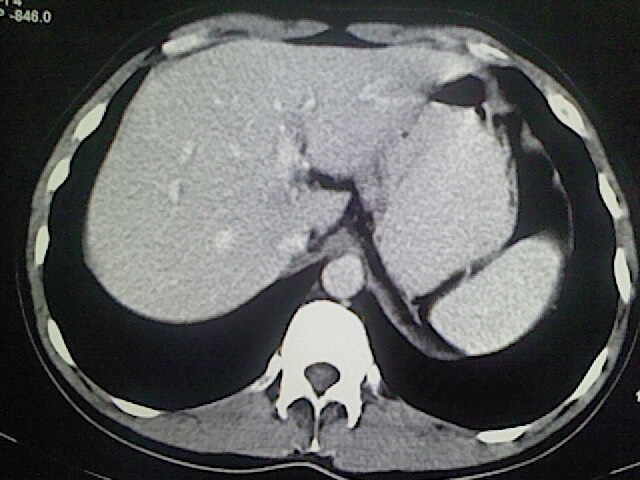

以下是引用卜一在2009-3-14 9:49:00的发言:[br]胆囊萎缩,胆囊壁不规则增厚,内部结构模糊,增强明显强化。另:肝左叶外侧段肝囊肿。支持:慢性胆囊炎!高度可疑:胆囊癌!

以下是引用余辉在2009-3-14 8:48:00的发言:[br]1)慢性胆囊炎。2)肝左叶外侧段肝囊肿。3)脂肪肝。[br]支持,胆囊萎缩,密度增高,不知b超具体有何提示,钙胆汁?结石?

以下是引用jiangjing在2009-3-14 10:18:00的发言:[br]1)慢性胆囊炎。2)肝左叶外侧段肝囊肿。3)脂肪肝。4.】建议行肝功能检查